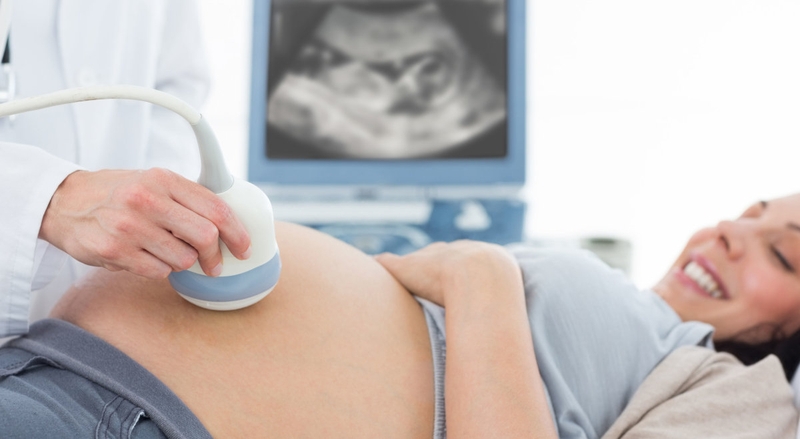

Tụ dịch màng nuôi: Nguyên nhân và cách điều trị 3 Thai phụ cần thăm khám bác sĩ định kỳ để nắm rõ tình trạng sức khỏe